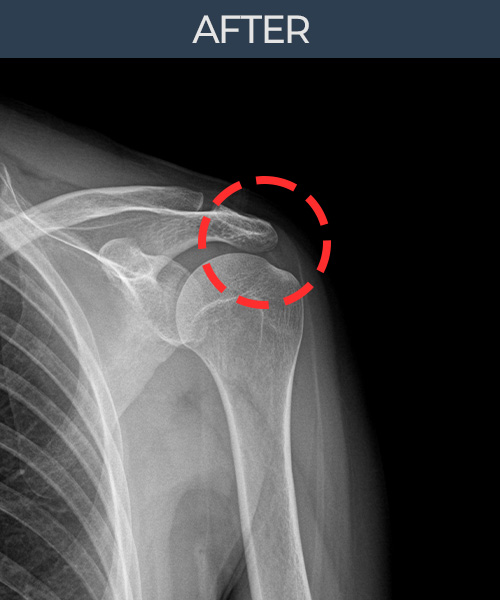

수천건의 수술 경험을 바탕으로 정확히 진단하여

인대파열을 비수술로 치료합니다.

플래티넘정형외과에서는 수술이 필요없는 인대파열만을

정확히 진단하여 특허받은 술기로 비수술로 치료합니다.